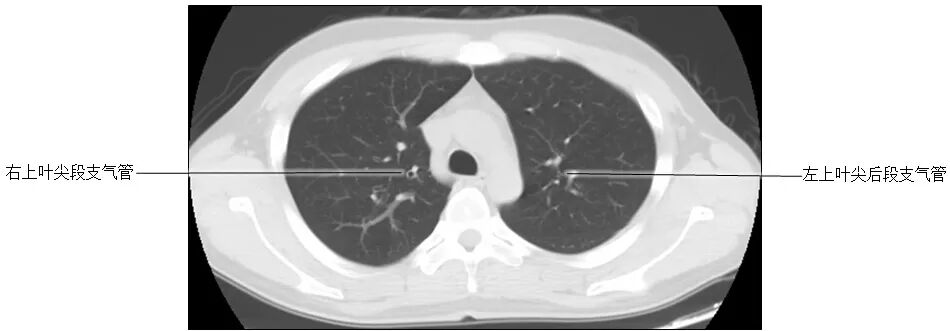

正常胸部CT影像是从横断面显示解剖和病变,可显示的结构包括胸廓、气管和支气管、肺、胸膜、纵隔和膈,CT的重建图像可从各个角度显示胸部解剖情况。不论采用何种图像显示方式,把握基本解剖结构都是必不可少的,一起学习胸部CT肺窗和纵隔窗的正常解剖。

胸部CT肺窗